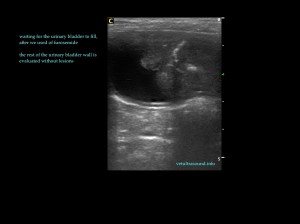

Σε όλα τα παρακάτω περιστατικά έγινε λήψη ούρου για την επιβεβαίωση της βακτηριδιακής κυστίτιδας. Τις περισσότερες φορές, λόγω συχνοουρίας, η κύστη δεν ήταν επαρκώς γεμάτη και έπρεπε να περιμένουμε 15 λεπτά περίπου ώστε να γεμίσει, με ή χωρίς τη χορήγηση φουροσεμίδης.

In all the following cases, urinary samples were taken for culture, in order to confirm the diagnosis of bacterial cystitis. In most cases the urinary bladder was almost empty due to polyuria, so we had to wait for about fifteen minutes, with or without the use of furosemide.

Τα πήγματα αίματος πολλές φορές μπορεί να προσομοιάζουν μάζες της ουροδόχου κύστης, ειδικά αν δεν είναι αρκετά γεμάτη ή δεν έχουν σχηματιστεί πρόσφατα. Σε αυτή την περίπτωση περιμένουμε να γεμίσει ώστε να εξετάσουμε:

Blood clots can resemble masses, especially when the urinary bladder is not fully distended or the clot was not recently formed.